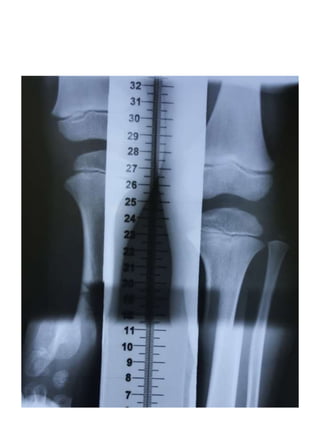

1393- 6 Y/O

cm Right left

PF 51.9 52.4

DF 28.6 25.1

FL 23.3 27.3 4

DT 9.1 1.4

TL 19.5 23.7 4.2

LL 42.8 51 LLD:8.2

PF 66.8 64.5

DF 40 33.2

FL 26.8 31.3 4.5

DT 22.6 7.2

TL 17.4 26 8.6

LL 44.2 57.3 LLD:13.1

1394-

8y/o

PF 79.2 74.2

DF 50.3 40.8

FL 28.9 33.4 4.5

DT 32 13.8

TL 18.3 27 8.7

LL 47.2 60.4 LLD:13.2

1395 - 9 y/o